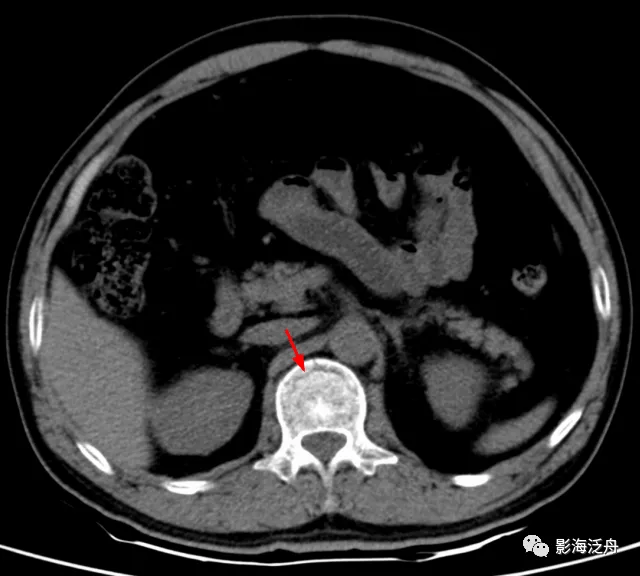

病例一:女 , 48岁 , 摔伤致腰背部疼痛、活动受限2天。

这个病例是非常特殊的 , 患者外伤史明确 , 但整体观察下来并没有看到明确的骨折征象 , 回过头反复阅片才在薄层胸部CT最后两个层面观察到椎体的细微骨折征象 , 而其余层面都是正常的 。 这样的病例 , 对于一些阅片习惯不好的朋友 , 漏诊率几乎是百分之百的 。 因为大部分阅片者往往不能较为均匀地去观察一组影像图片 , 总是会在一组图像刚开始和快要结束的时候不由自主地加快鼠标的滚动速度 , 一不小心就错过了重要的内容 。 所以 , 如果你也有类似的习惯 , 那就要当心了!